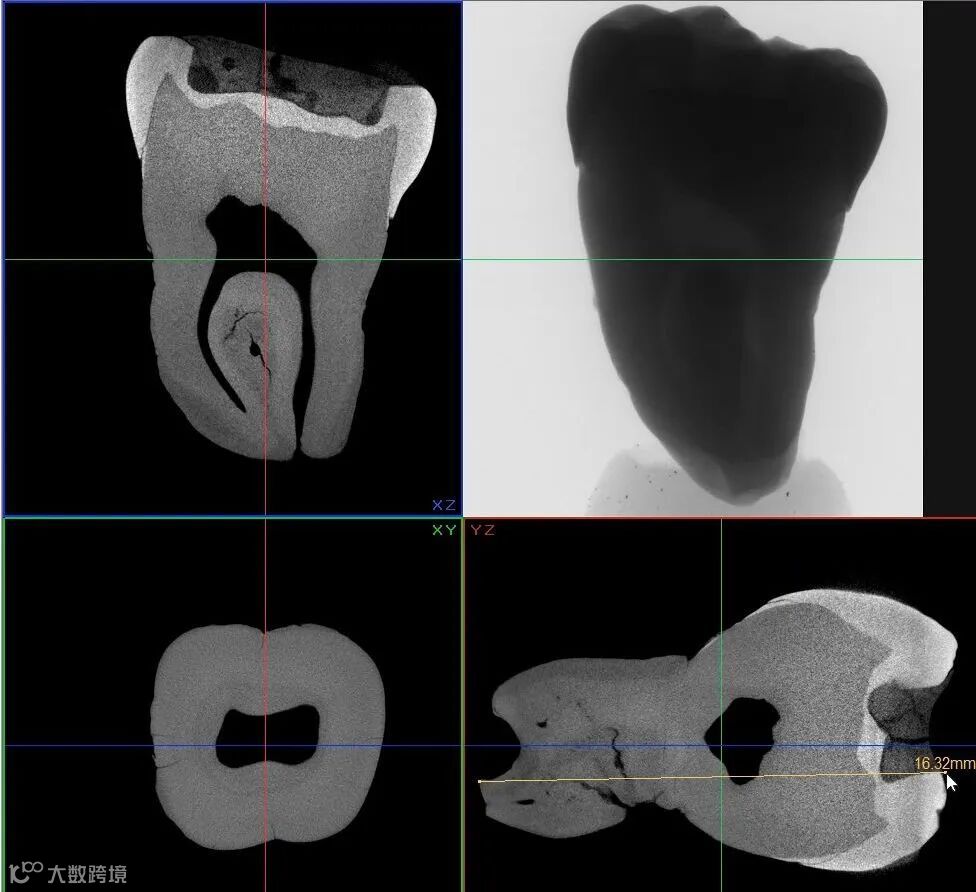

使用 Neoscan台式显微CT以 9.8 μm 像素大小扫描一颗臼齿,显示牙本质和牙釉质中存在裂纹,填充材料被腐蚀